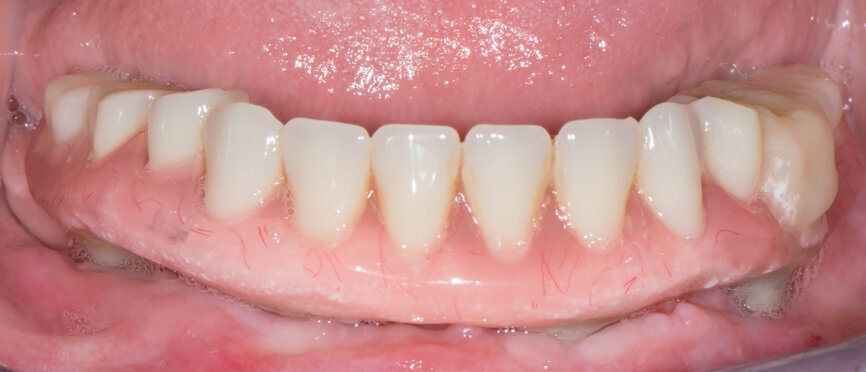

Two months after the implant placement, impressions were taken and the precision was checked with a verification jig (Figs. 25 & 26). The vertical dimension of the provisional prosthesis was followed when mounting the casts in the articulator (Figs. 27 & 28). The analogue set-up was tried in (Fig. 29), then scanned by the Straumann CARES 7 series scanner together with the model. The framework on Straumann Variobase screwretained abutments was designed in CARES Visual following the set-up anatomy (Fig. 30), then milled from titanium (Fig. 31). The passive fit of the framework was checked, and it was then veneered with resin with the denture teeth in place (Figs. 32 & 33). Variobase abutments were cemented into the prosthesis, and the final restoration was tightened to 15 Ncm (Fig. 34). Screw holes were closed with PTFE tape and composite.